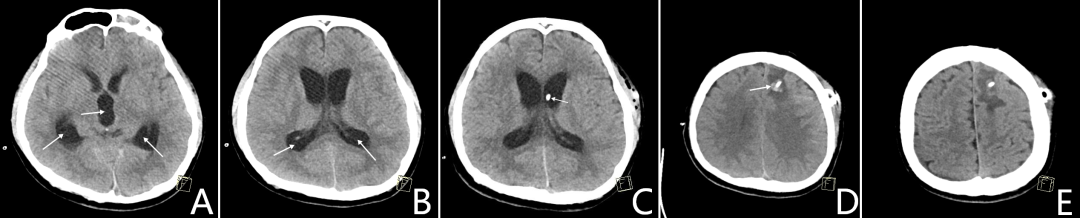

患者住院1个月,又出现慢性脑积水,再次手术势在必行。但此时患者仍在抗血小板治疗期,手术意味着出血风险极高;停药则可能引发脑梗死。进退之间,容不得半点犹豫。神经外科团队选择迎难而上——选择在持续用药前提下,迎险实施手术。术后虽出现少量脑出血,但凭借严密监测、精准调控分流装置压力与动态复查CT的多重保障下,最终将出血控制并吸收,涉险过关。